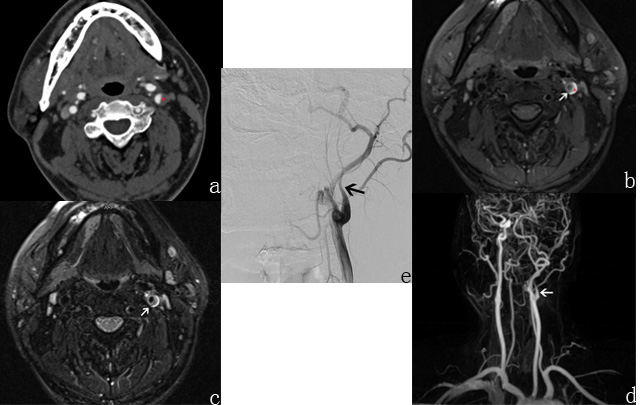

Fig 1. 39-year-old man with headache for 10 days diagnosed as left carotid artery dissection by DSA eventually. (a) Axial CTA image showed eccentric low density (red star). (b, c) Axial T1-weighted and T2-weighted MRI images showed crescent-shaped high signal caused by a mural hematoma surrounding the lumen (red star) and intimal flap (white arrow) clearly. (d) Reconstruction contrast-enhanced MR angiography image showed tapered occlusive lumen of the left carotid artery (white arrow). (e) DSA image demonstrated the dissection (black arrow).